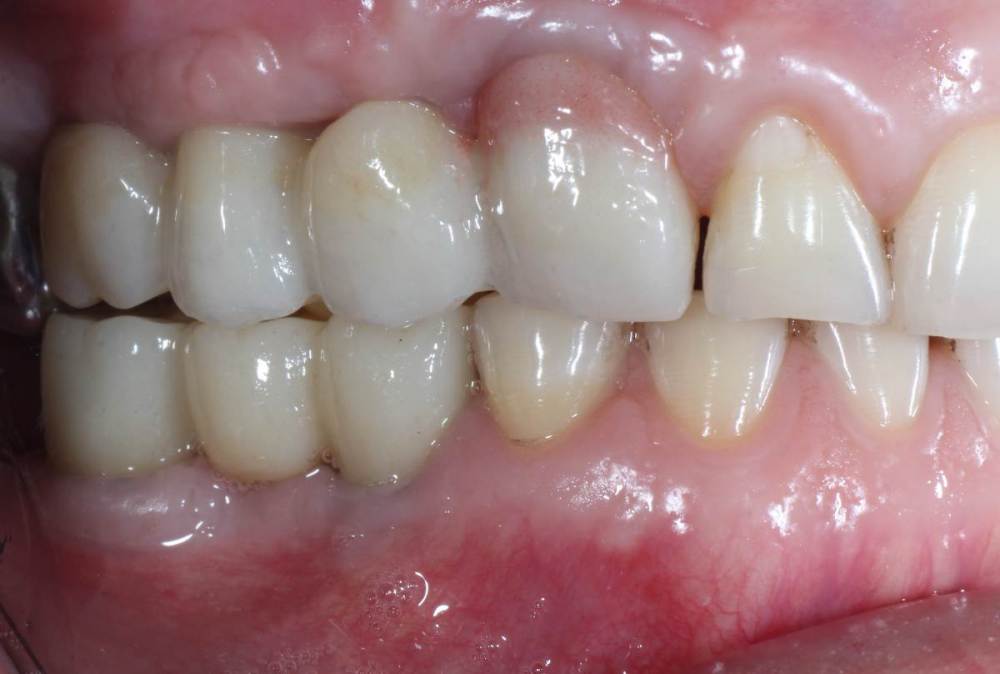

kuziy12 Опубликовано 2 ноября, 2020 Поделиться Опубликовано 2 ноября, 2020 Имплантация с синус лифтингом. Беда с позицией 2.3. Коронки на cad\cam, наносил розовую керамику и красил все сам. Сваливать не на кого) До: После имплантации: Формики: Десна: Постоянная конструкция: Улыбка: 3 Ссылка на комментарий

kuziy12 Опубликовано 9 октября, 2021 Автор Поделиться Опубликовано 9 октября, 2021 Дабы не плодить темы, выложу тут. Докрутил пациента полностью)) Ортопедия тоже моя. От переустановки импланта в области клыка отказалась. Ссылка на комментарий

Карен Аванесов Опубликовано 11 октября, 2021 Поделиться Опубликовано 11 октября, 2021 Ну вот, поздравляю Вас, получили благословение от Большого Зеленого, таперча работе служить 10 лет не меньше. 16 часов назад, Большой Зеленый сказал: Проблемы будут обязательно... а меня стертый клык насторожил, а работа жить будет, во рту чисто. 1 Ссылка на комментарий

kuziy12 Опубликовано 12 октября, 2021 Автор Поделиться Опубликовано 12 октября, 2021 11.10.2021 в 05:28, Большой Зеленый сказал: Проблемы будут обязательно... Спасибо за подсказку, а я думал вы уже потерялись где-то, давно вас на форуме не видно 22 часа назад, Карен Аванесов сказал: Ну вот, поздравляю Вас, получили благословение от Большого Зеленого, таперча работе служить 10 лет не меньше. а меня стертый клык насторожил, а работа жить будет, во рту чисто. с суставом проблемы, пац заниматься не хочет Ссылка на комментарий